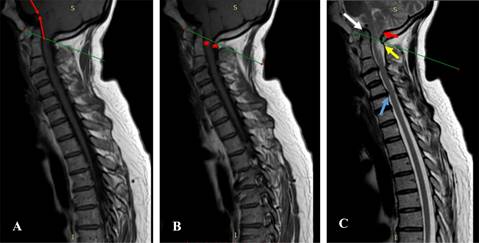

Figura 3: A) Corte sagital de resonancia magnética nuclear de columna (RMNC), proyección T1, en línea roja, ángulo pontomedular, no muestra kicking; línea verde, plano de McRae. B) RMNC, en T1, corte sagital; en asteriscos rojos, espacios libres de unión bulbo medular, se muestra espacio canal raquídeo sin compresión. C) RMNC en T2, corte sagital; flecha blanca, aparato cruciforme abombado, evidencia de hiperlaxitud; flecha roja, amígdalas cerebelosas, sin descenso; flecha amarilla, hiperintensidad en cordón posterior; flecha celeste, abombamiento del ligamento longitudinal posterior por protrusión discal contacta con la médula, pero no hay datos clínicos de mielopatía.